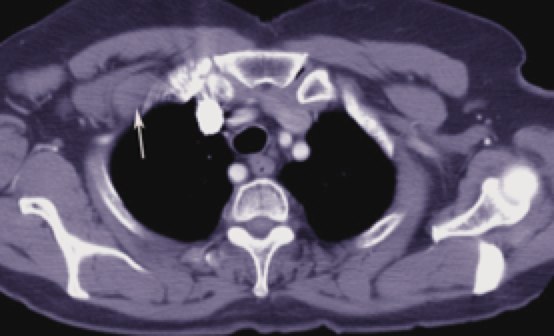

Fields and treatment volumes

CT simulation is very useful to precisely delineate the target volumes. The IMN vessels are found within the first 3 intercostal spaces and are the region where the IM nodes are at highest risk. Using the IM vessels. The depth of the Level III axillary and supraclavicular nodes is also variable. The depth can be easily determined from CT imaging. Contouring these nodes in the treatment planning system can insure they are adequately treated. Studies of treatment planned patients using a 6 MV anterior oblique supraclavicular field prescribed to a depth of 3 cm can significantly underdose nodes in patients who are overweight or obese.